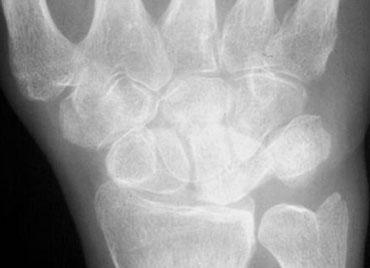

Phân tích:

Ca lâm sàng bên trái cho thấy thoái hóa khớp nặng tại khớp STT (thuyền-thang-thê) và khớp CMC1 (cổ tay-bàn tay ngón 1) kèm bán trật khớp. Các cung cổ tay bình thường và có tính song song bình thường. Xương thuyền bị kéo dài, cho thấy nó đang nghiêng ra phía sau (dorsally tilted).

Trên tư thế nghiêng, chúng ta có thể thấy xương nguyệt cũng nghiêng ra phía sau. Hàng cổ tay gần di chuyển như một khối thống nhất, do đó không có sự phân ly.

Chẩn đoán cuối cùng: DISI không phân ly (non-dissociated DISI) kèm thoái hóa khớp và bán trật khớp STT.